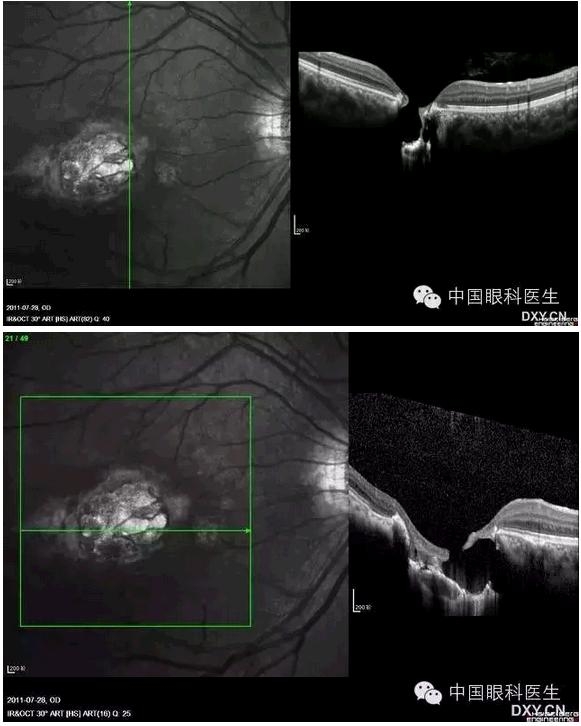

先天性黄斑缺损

玻璃膜疣OCT示视网膜色素上皮隆起,下方为轻中度反射,与脉络膜反射无区别,从隆起的视网膜色素上皮延伸到脉络膜。